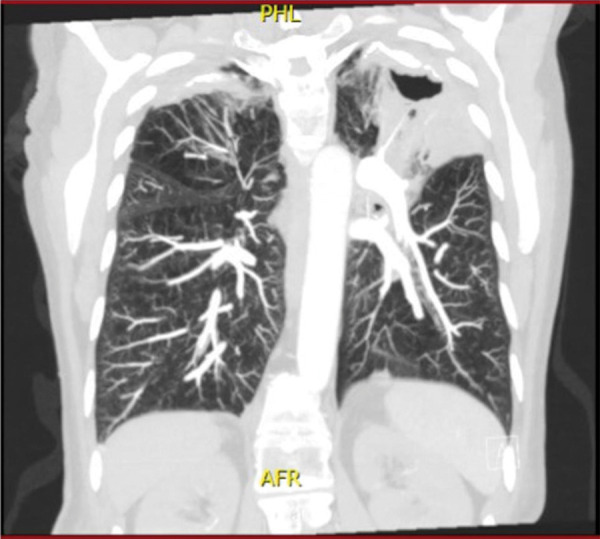

我们报告了一例女性非典型抗肾小球基底膜(anti-GBM)肾炎患者的病例,她同时患有肺分枝杆菌感染。肾活检显示新月体肾小球肾炎伴有50%的活动性新月体和线性IgG染色,但未检测到循环中的抗GBM抗体,患者也没有肺出血。尽管患者接受了抗生素、皮质类固醇激素和血浆置换术三联疗法治疗,但肾功能仍未恢复。一年后,她仍在进行维持性透析,但仍未摆脱阿维菌感染。

We present the case of a woman with atypical anti-glomerular basement membrane (anti-GBM) nephritis associated with concurrent pulmonary infection with Mycobacterium avium. A kidney biopsy showed crescentic glomerulonephritis with 50% active crescents and linear IgG staining, but no circulating anti-GBM antibodies were detected, and the patient did not have pulmonary hemorrhage. Despite treatment with a triple-regimen of antibiotics, corticosteroids, and plasmapheresis, the patient did not regain kidney function. One year later she is on maintenance dialysis and has still not cleared the infection with M. avium.